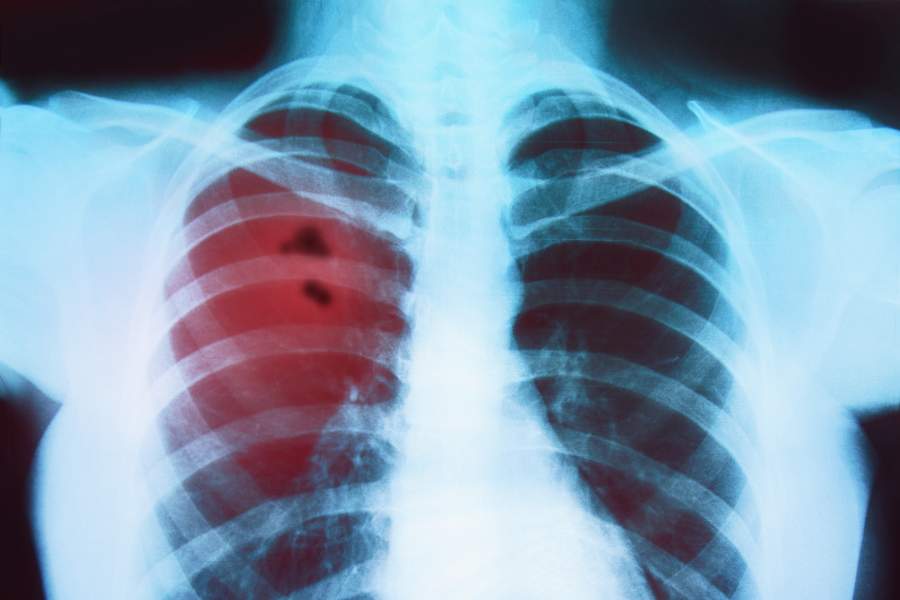

Bronchitis is an inflammation of the mucous membranes of the bronchi (the larger and medium-sized airways that carry airflow from the trachea into the more distal parts of the lung parenchyma). Bronchitis can be divided into: 1. Acute 2. Chronic Acute bronchitis is characterized by the feeling of cough or small sensation in the back of the throat. It can be with or without the sputum (mucus that is expectorated, or "coughed up", from the respi. Read more...